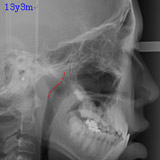

アデノイドの大きさについて

左はほぼ正常の状態で、わずかな腫れが認められますが問題ありません。

真ん中は軽度の腫れで、気道(空気の通り道)を少しふさいでいます。この場合は経過観察、または必要があれば耳鼻科で管理していただきます。

右は腫れが強く、気道をふさいでいます。この状態では鼻呼吸が困難であり、歯列、顔面発育にも影響がでる可能性が大きくなります。耳鼻科での治療を強くお勧めます。